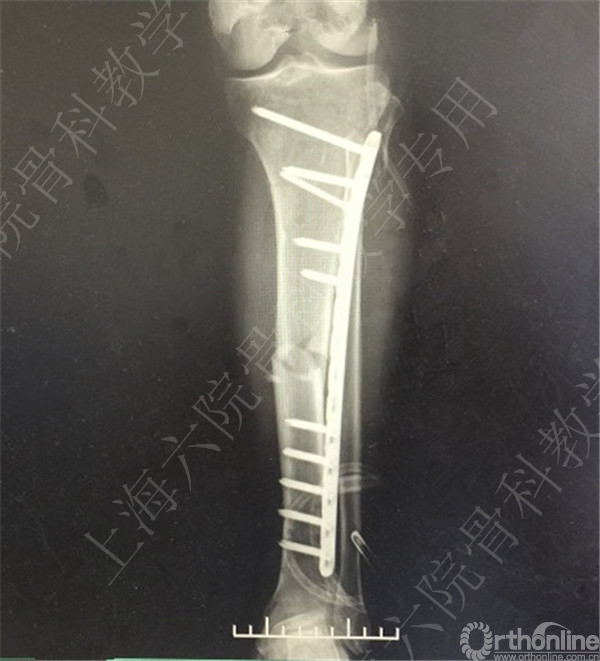

患者择期行左胫骨切开复位内固定术+髂骨异体骨植骨。

术后X线摄片示:骨折对位对线可,内固定牢靠,左胫骨对线可。

医方第一次跟换内固定术中,未纠正左胫骨立线,骨折对位对线差,未纠正成角,导致术后内固定失效,骨折成角变大。医方存在手术方式不当,手术操作不当,术后并发症观察、处理不当,对疾病评估不足,告知缺陷等过失。